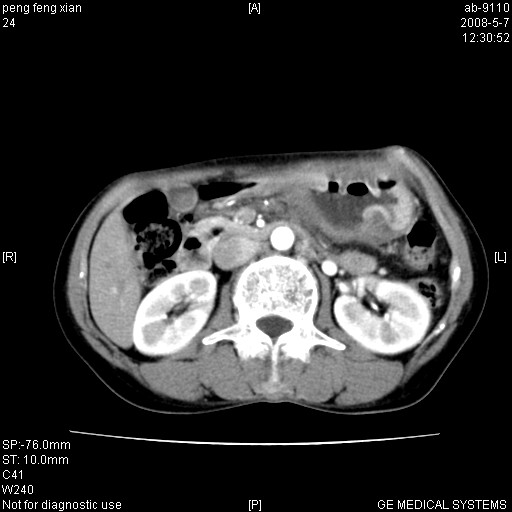

女,56岁。b超左一腹包块,考虑胃肠道肿瘤。

胃底占位待出;右肾结石?

胃体部胃壁增厚,不均匀性强化,与胰腺分解欠情.

考虑:胃癌,胰腺受侵待除外.